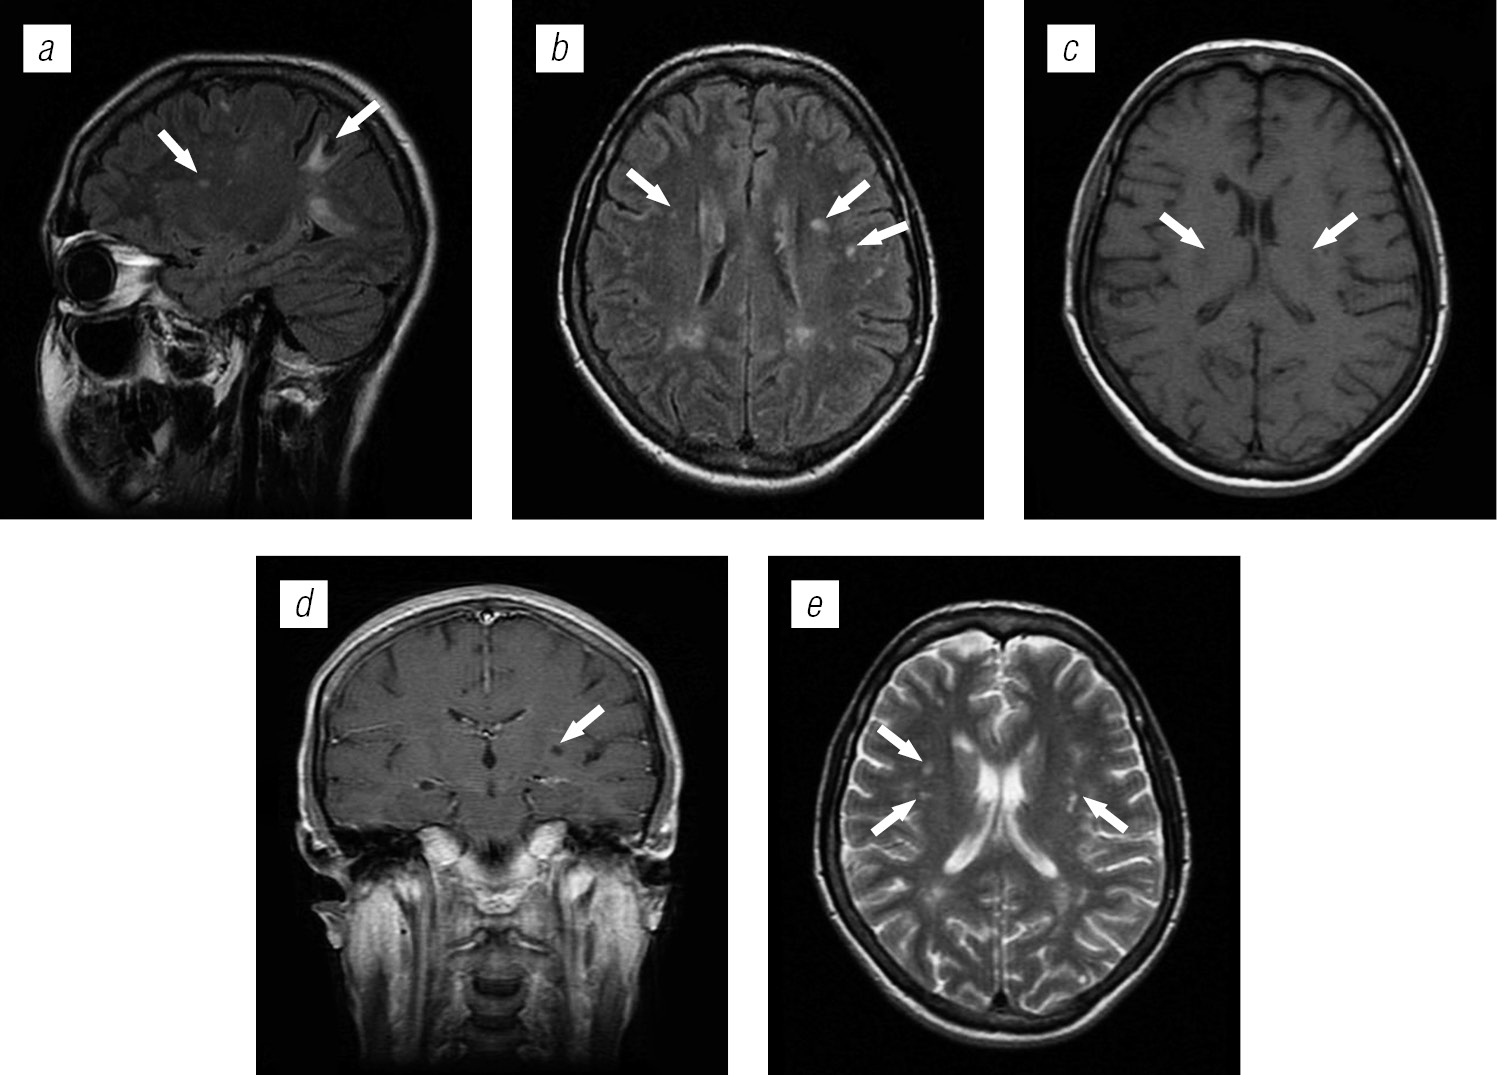

Структура оппортунистических и вторичных заболеваний была представлена токсоплазмозом головного мозга (18,3 %), герпесвирусными поражениями (12,2 %), прогрессирующей мультифокальной лейкоэнцефалопатией (10,24 %), нейроинфекцией неуточненной этиологии (12,2 %), криптококкозом (4,39 %), туберкулезом (2,44 %), лимфомой головного мозга (2,44 %), МАК-инфекцией (0,24 %).